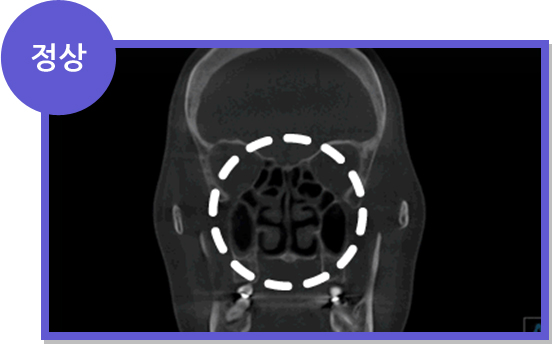

CT

CT

A.구조 이상에 의한 비염

- 비중격만곡증에 의한 비염

- 비중격 연골이 휘어서 생긴 비염은 휘어진 비중격 연골을 교정하면서 비염 수술을 같이 해야 합니다.

세계적으로 인정받는

Amorphous Silicon Flat Panel

센서를 사용하여 선명한 고화질로

환자의 상태를 볼 수 있어

정확한 진단이 가능한 CT로 진단

세계적으로 인정받는

Amorphous Silicon Flat Panel

센서를 사용하여 선명한 고화질로

환자의 상태를 볼 수 있어

정확한 진단이 가능한 CT로 진단